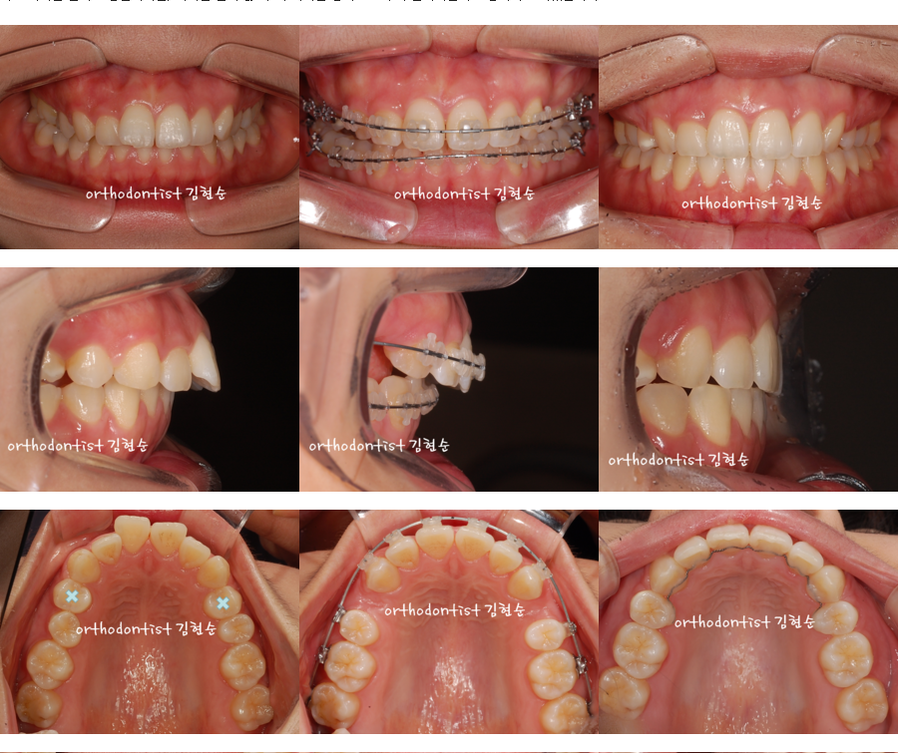

치료 계획은 발치 교정입니다만, 아래는 뽑지 않고, 위 치아만 양측으로 두개 발치하면서 교정하기로 하였습니다. .

치료 계획은 발치 교정입니다만,

아래는 뽑지 않고,

위 치아만 양측으로 두개 발치하면서

교정하기로 하였습니다.